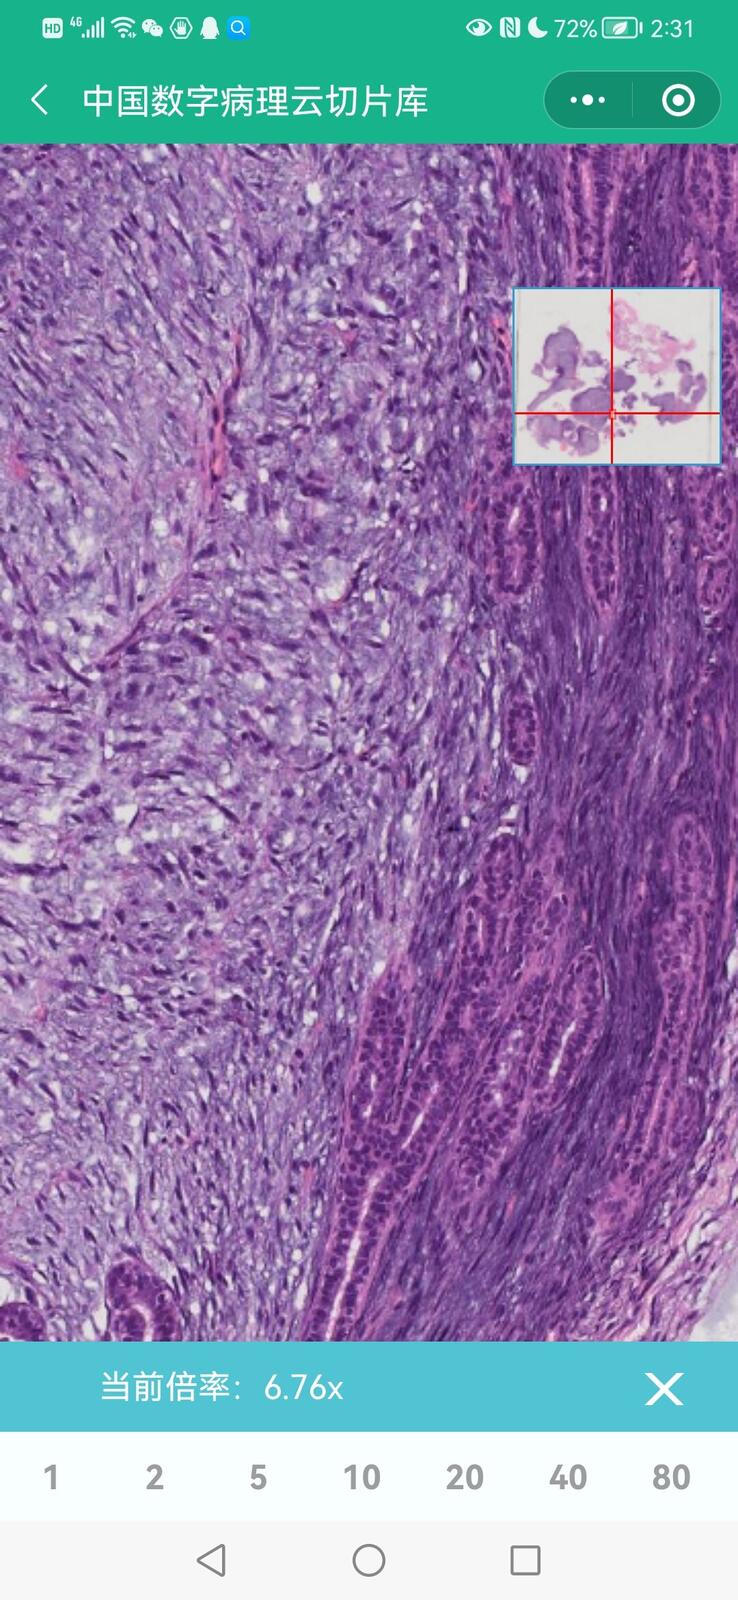

乳腺多形性脂肪肉瘤

乳腺叶状囊肉瘤